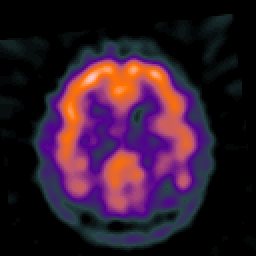

Alzheimer's disease: overlay -- Slice #36

[Home][Help][Clinical] Slice 36